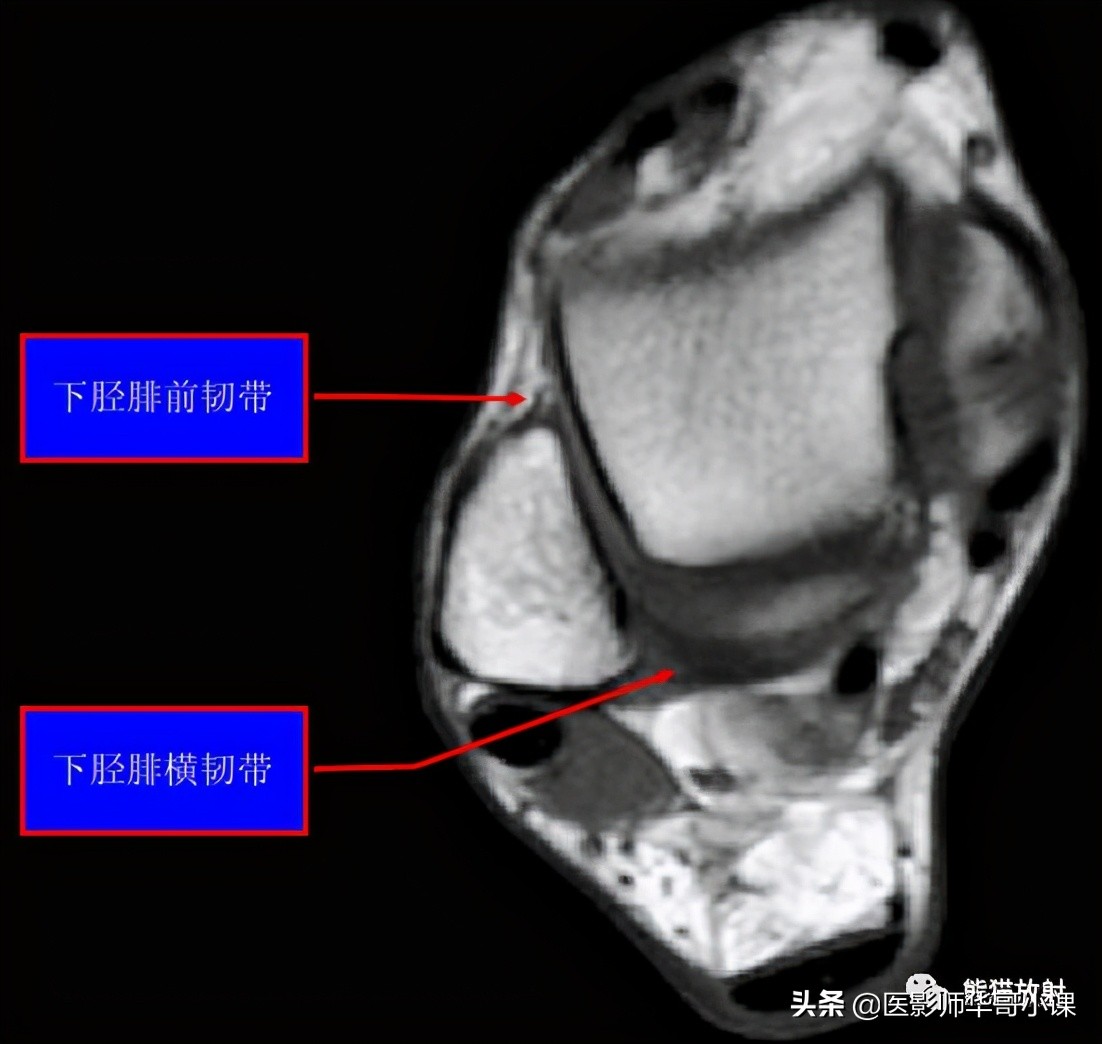

下胫腓联合韧带

胫腓骨远侧关节面由腓骨远端的凸面和胫骨远端的凹面组成,由胫腓韧带链接,关节内无软骨结构。 远端胫腓联合韧带由四部分韧带组成,包括: 骨间韧带,下胫腓前韧带,下胫腓后韧带,下横韧带。

骨间韧带由骨间膜远端增厚形成。下胫腓前韧带起于胫骨结节的前外侧,止于腓骨脊的前侧。下胫腓后韧带起于胫骨脊后侧,止于外踝后缘。下横韧带组成下胫腓后韧带的下半部分,可视为下胫腓后韧带的一部分。

下胫腓前韧带(35%),下胫腓后韧带深层(33%)对踝关节稳定性作用最大,其次是骨间膜(22%)和下胫腓后韧带浅层(9%)。

下胫腓联合远端韧带结结构,包括:骨间韧带(IOL),下胫腓前韧带(AITFL),下胫腓后韧带(PITFL),下横韧带(ITL)。